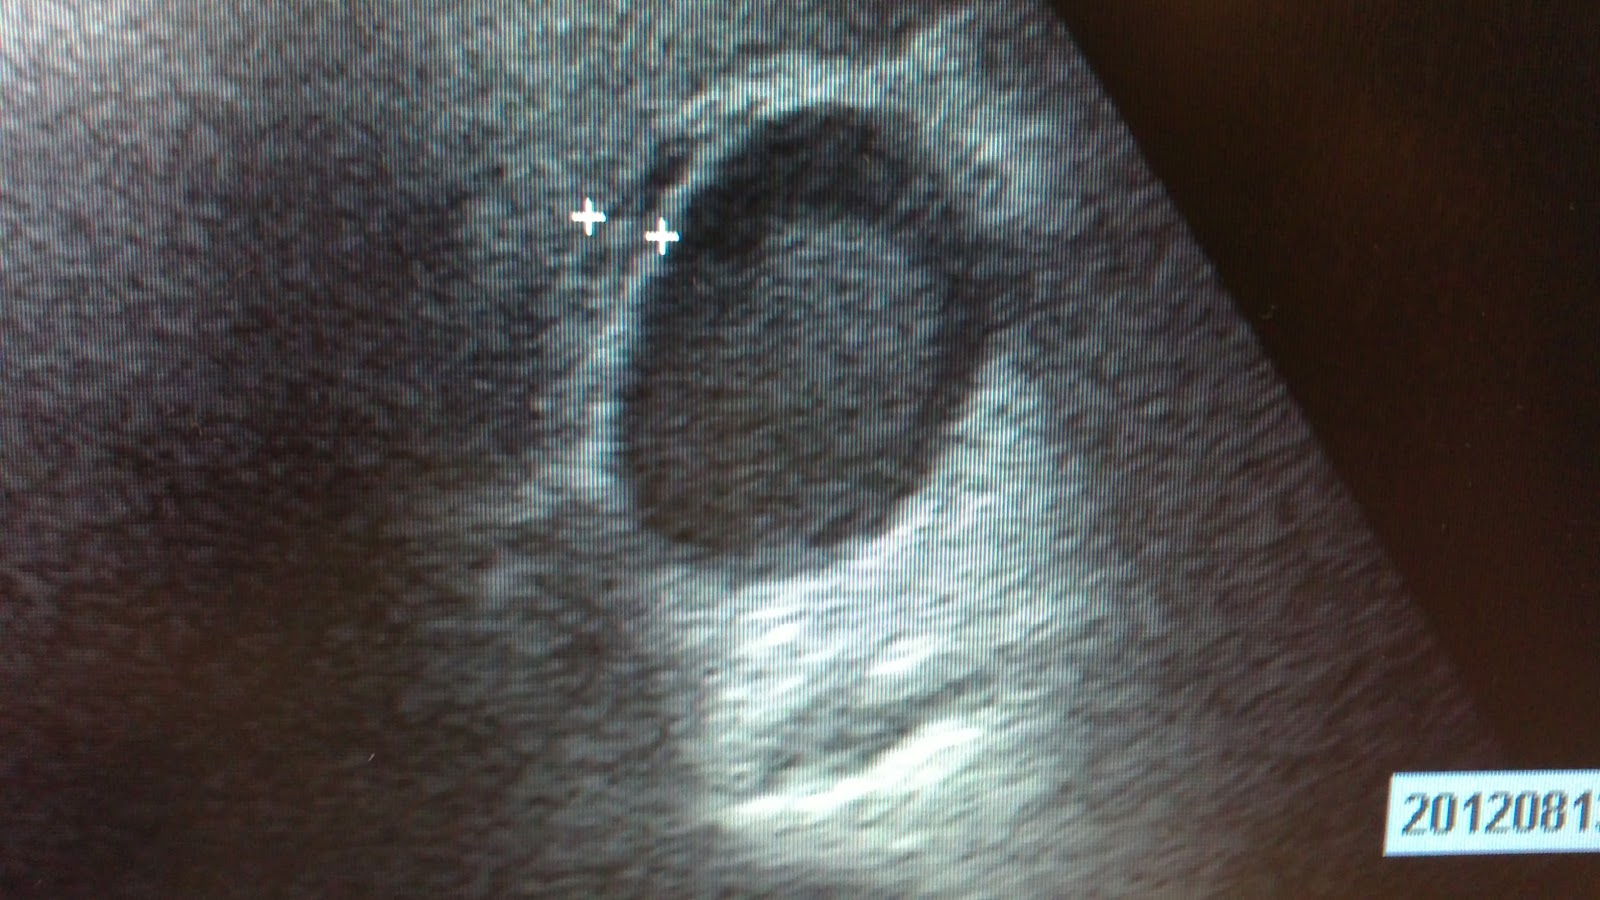

| Barro biliar e imágen calcificada por litiasis biliar Foto de Jose A Cortés |

Ecografía abdominal realizada en el Centro de Salud: hígado de ecogenicidad homogénea y aumentada de forma difusa compatible con esteatosis, vesícula de 9 cm de diámetro longitudinal, con presencia de acúmulo hiperecogénico sin sombra acústica posterior que ocupa gran parte de la vesícula biliar compatible con barro biliar e imágenes hiperecogénicas con sombra acústica posterior, compatibles con litiasis vesicular. Engrosamiento de la pared vesicular en capas de cebolla, compatible con edema de pared vesicular.